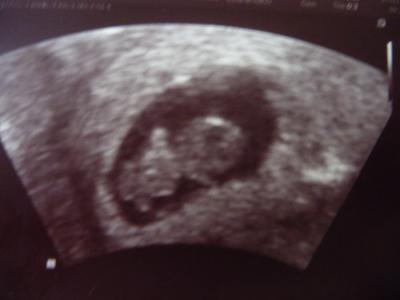

Heute war ich auch wieder an der Reihe. Hatte tierische Angst, da ich in der 9. Woche bin und letztes Mal hatte ich in der 9. Woche die FG. Aber es ist alles bestens. Unser Gummibär ist 1,86 cm groß und absolut zeitgerecht entwickelt. Das Herz hat auch fleißig geblubbert. Jetzt bin ich erstmal wieder beruhigt. Muss wieder in 2 Wochen hin. Ein Bild von unserem Gummibär habe ich eingefügt (falls es klappt).

Bild zu Ich bin schon wieder da vom FA-Termin - Forum für September - Mamis